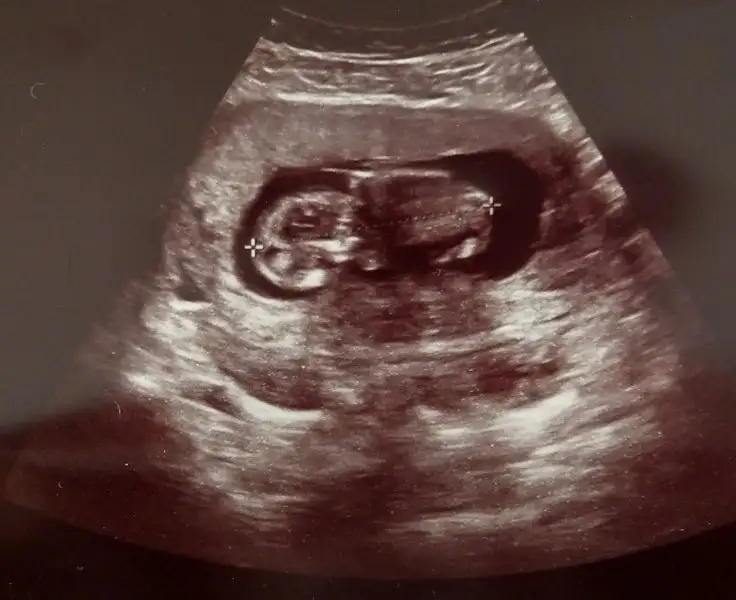

Bebek hiç gözükmüyor kiHanimlar banada bi cinsiyet tahmin yaparmisiniz hic migde bulantisi yasamadim hamileligim boyunca cok sukur basim agrisi cok oluyordu sadece

bebegin vucudu gozukmuyor sadece kfasini anlayabildim benHanimlar banada bi cinsiyet tahmin yaparmisiniz hic migde bulantisi yasamadim hamileligim boyunca cok sukur basim agrisi cok oluyordu sadece

Aynen bebeğin son hali, keseye o kadar alıştım ki :)Sadece kese mi icinde bebek olmasi mi gerekiyo?

Aynen bebeğin son hali, keseye o kadar alıştım ki :)

:) Değişik durmuş tamamen sallıyorum Kız.Bu 12+2deki hali